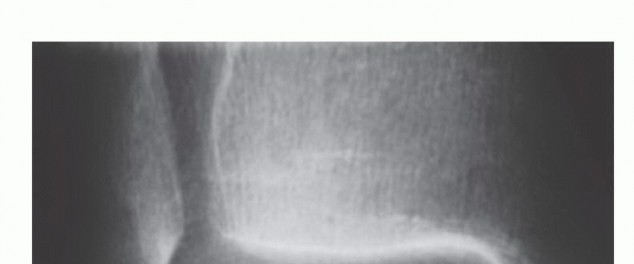

DEFINITION The terminology of osteochondral lesions is not uniform: Transchondral fractures, osteochondral fr…